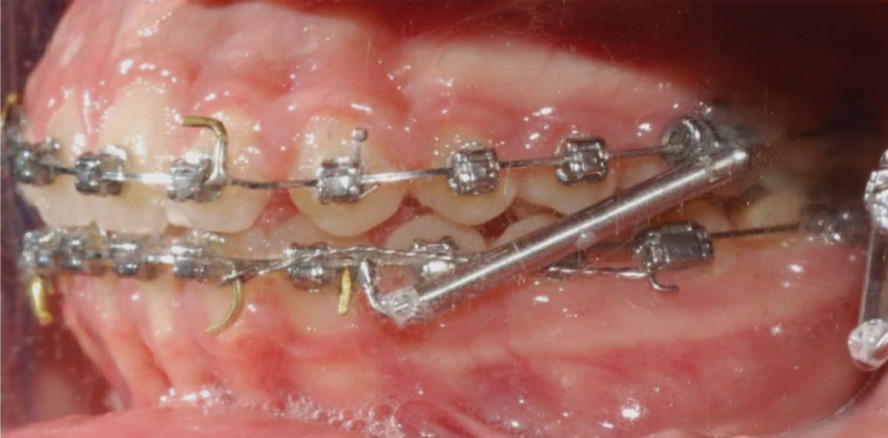

Da die Patientin kaum mitarbeitete, wurden beidseitig Klasse II-Korrektoren eingesetzt mit Fixierung auf einem .019'' x .025'' Stahlbogen (Abb. 13). Nach zwei Monaten war ein stabiles Klasse I-Verhältnis der Prämolaren und Molaren erreicht und die Klasse II-Apparatur wurde wieder entfernt (Abb. 14).